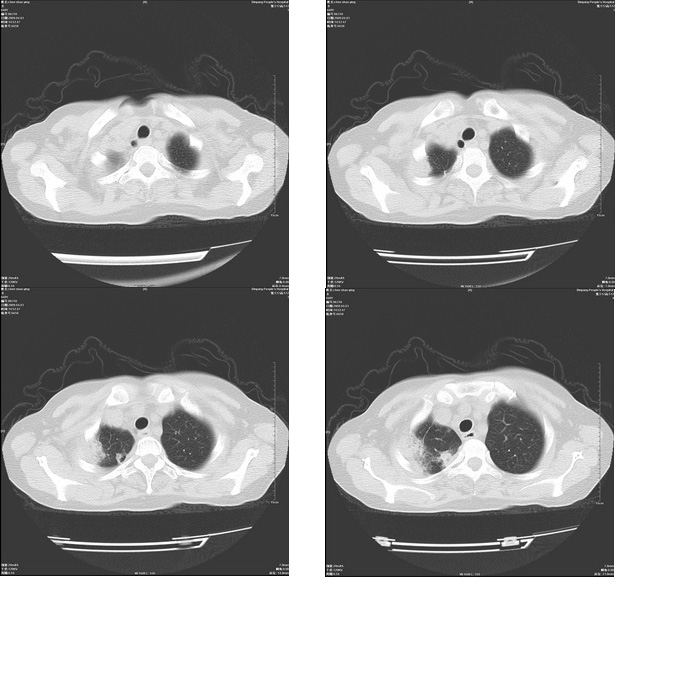

患者,女,48岁,发热伴陈发性咳嗽5天,偶尔痰中带血。体温约38°~40°;白细胞明显减低0.85x10的9次方/升。入院后抗炎、抗痨一周复查病灶明显进展。

右上肺后段实变影,内见支气管气象,肺门未见软组织肿块,气管前方有肿大淋巴结。左下肺见多个类圆形结节影。考虑:1.右上肺后段大叶性肺炎,需进一步检查病原体种类,应多询问病史,条件许可考虑做纤支镜检查2.左下肺结节影性质待定

考虑右上肺后段大叶性肺炎不除外结核,伴双肺结节播散灶,希定期复查。

右肺于酪性肺炎并左肺播散。

考虑两肺继发性肺结核(右肺上叶干酪性肺炎?)。